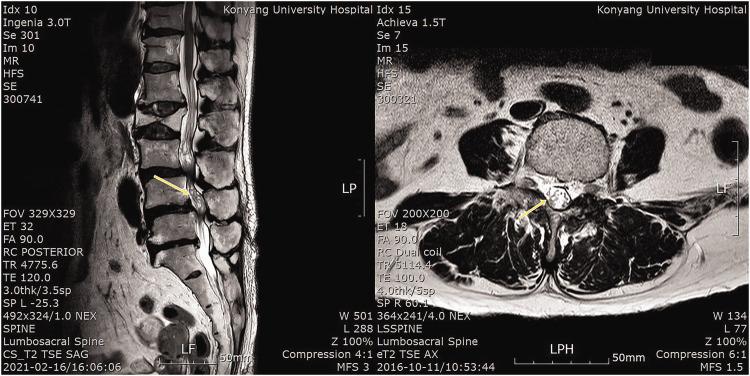

骶管阻滞治疗伴有神经根冗余综合征的椎管狭窄症的疗效。

Effectiveness of caudal block in patients with spinal stenosis accompanied by redundant nerve root syndrome.

Redundant nerve root syndrome (RNRS) is characterized by tortuous, elongated, and enlarged nerve roots in patients with lumbar spinal stenosis. This study was performed to evaluate the effects of caudal block in patients with RNRS and assess factors associated with RNRS.

神经根冗余综合征(RNRS)的特征是腰椎管狭窄症患者的神经根迂曲、延长和增粗。本研究旨在评估骶管阻滞对 RNRS 患者的疗效,并评估与 RNRS 相关的因素。